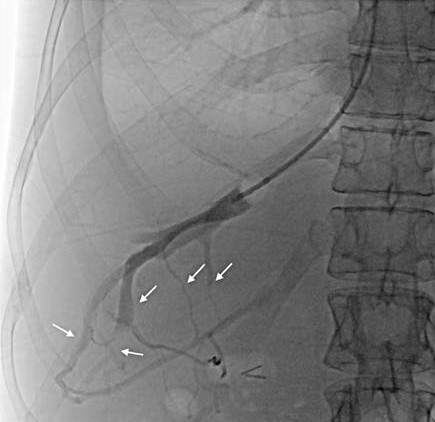

A 61-year-old man previously diagnosed with MetALD and prior oxaliplatin-based chemotherapy presented in 2017 with variceal upper gastrointestinal bleeding. Although imaging suggested cirrhosis with portal vein thrombosis, liver stiffness was low (LSM 7.7 kPa) and HVPG was 9 mmHg. Inconsistencies in the diagnostic work up led us to perform a liver biopsy, which showed portal abnormalities with focal sinusoidal dilatation and no fibrosis.